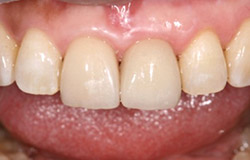

インプラントで噛み合わせの再構成を伴った症例。

治療後のメンテナンスを行わないと

周囲炎になるリスクあり。